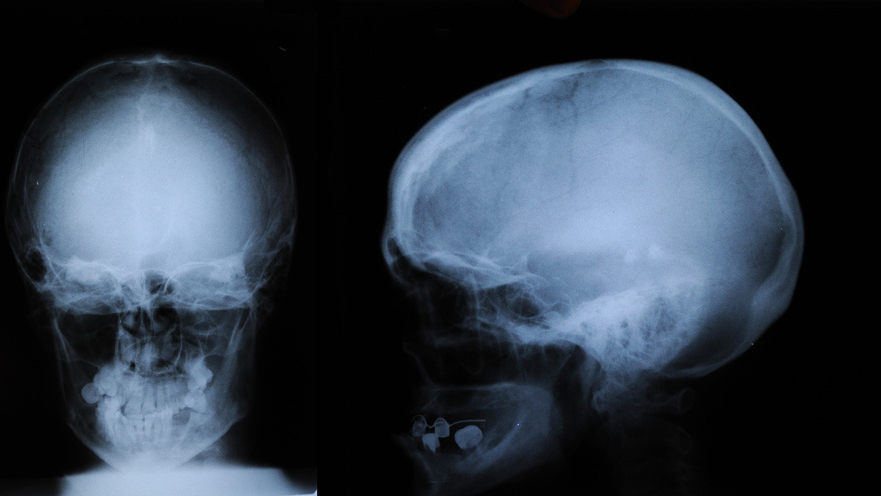

Анатомия детского черепа: Рентгеновские снимки и описание